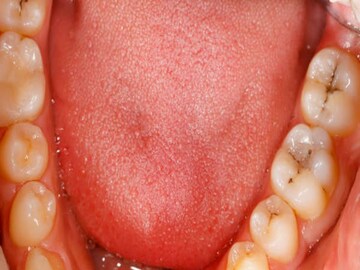

মুখে সাদা দাগ

মুখের ভিতরে সাদা কিংবা কখনও কখনও লাল দাগ ক্যানসারের ইঙ্গিতবাহক হতে পারে। যদিও এর পিছনে গ্যাসট্রিক সমস্যা কিংবা মুখের সংক্রমণের মতো বিভিন্ন কারণও থাকতে পারে। কিন্তু যদি এটি স্বাদ কিংবা কথাবার্তাকে প্রভাবিত করে তাহলে চিকিৎসকের পরামর্শ নেওয়া উচিত।